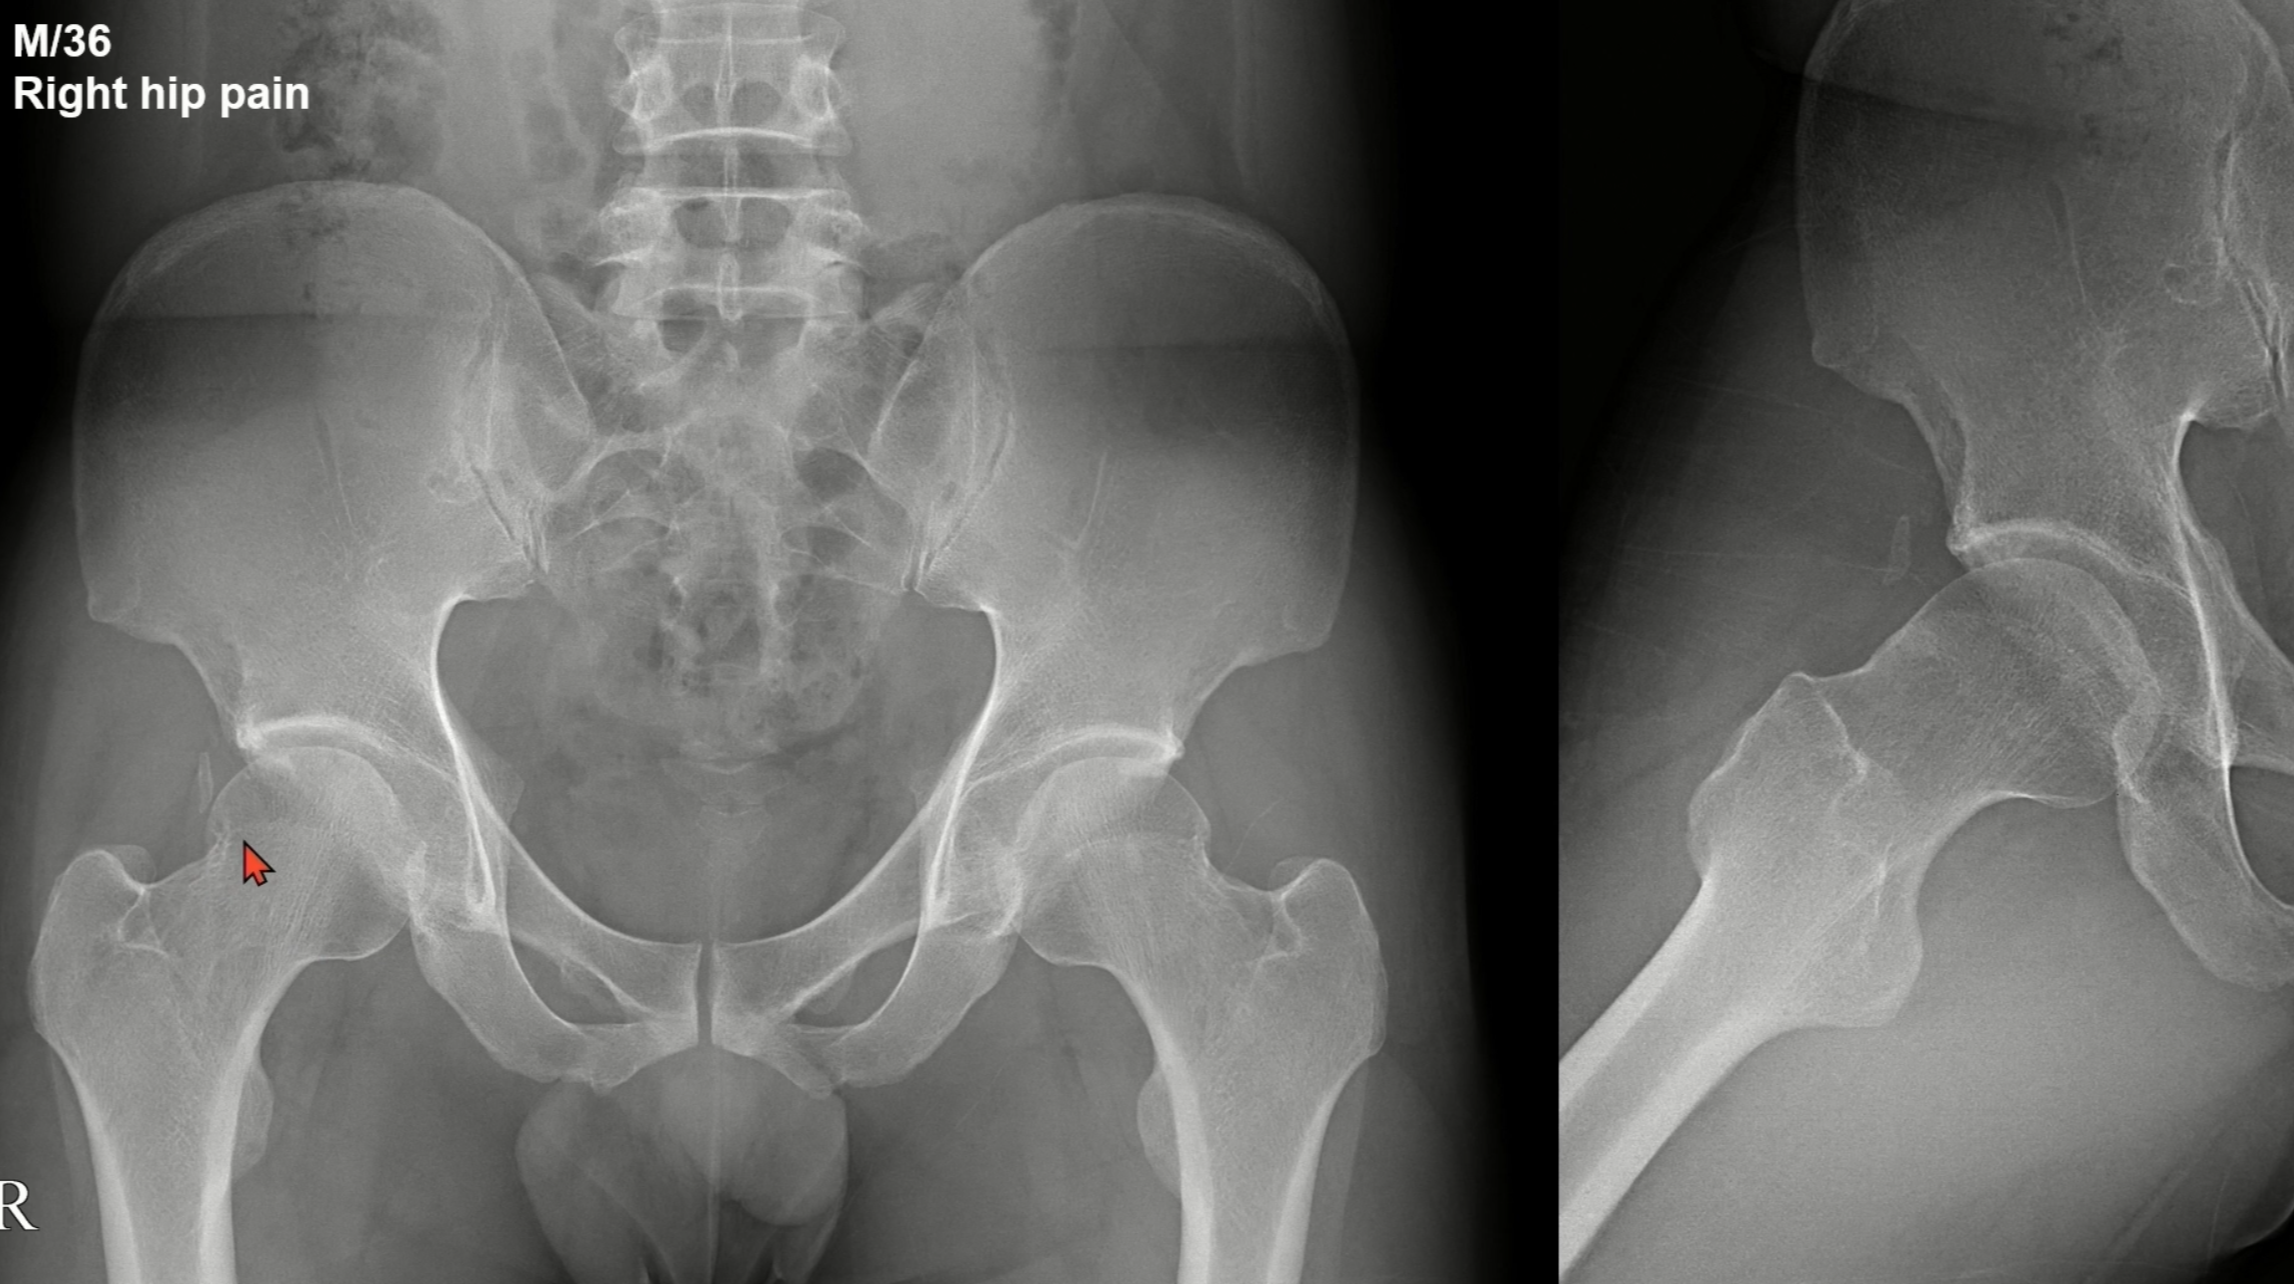

3. CAM type FAI의 영상학적 진단

CAM type FAI 여부는 1) Alpha angle, 2) head-neck offset를 통해서 진단할 수 있습니다.

먼저, Alpha angle은 55도 넘어가면 진단할 수 있습니다.

Alpha angle은 구형이 아닌 각도를 측정합니다. Head의 중심과 Neck의 중심을 잇는 선과 Head에서 구형이 이게 되는 지점까지의 각도로 측정합니다.

두번째로 head-neck offset은 8-10mm 이하일 때 진단할 수 있습니다.

offset가 크다는 뜻은 구가 살아있다는 뜻이기 때문에, 반대로 offset가 특정한 값 이하로 내려가면 head/neck juction에 cam type deformity가 있다는 뜻으로 이해할 수 있습니다.